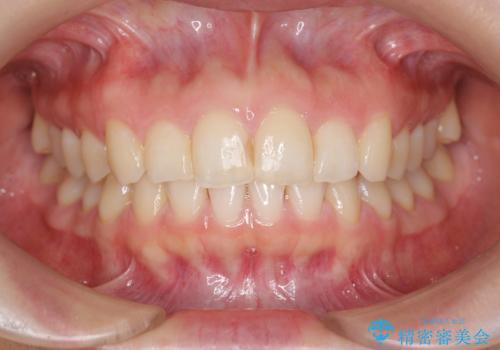

前歯のガタつきをきれいに マウスピース矯正治療

- 「前歯のガタつきをきれいにしたい。」と矯正治療を希望され来院されました。

前歯のガタつきをワイヤー部分矯正、上顎前突の咬合関係を後方移動することで理想的な咬合関係を確立します。

上顎の全体的な後方移動を実現するためにマイクロインプラントを併用したゴムかけを行ったことで理想的な咬合関係を確立することができました。